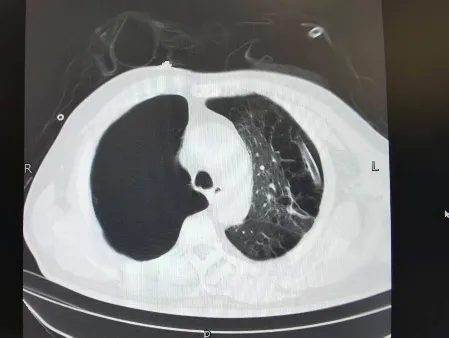

术前肺CT

放射科专家分析影像资料后指出,患者右胸巨大直径约8cm,占据右侧胸腔55%,且与肺门血管、胸膜存在多处粘连,术前需标记粘连位置,避免术中损伤血管;左胸术后残余胸膜增厚,可能增加肺复张难度。通过三维重建影像,清晰呈现病灶与周围组织的解剖关系,为手术精准操作提供关键依据。